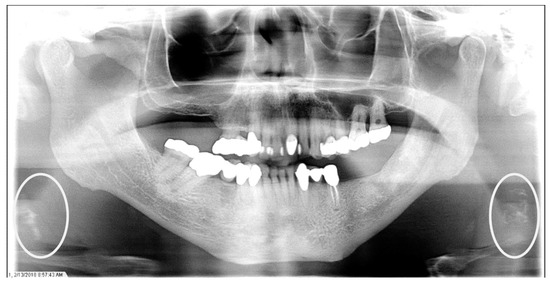

The characteristics of the CAC patients are presented in Table 1. Between 2014 and 2023, there were 559 patient records with the terms “carotid artery calcification” or “carotid” or “calcification of the carotid artery” noted. After the panoramic radiographs were reviewed, 314 patients were confirmed to have a diagnosis of CAC (including 26 patients with a history of carotid endarterectomy). The remaining 245 patient records were excluded because of the absence of detectable CAC on PRs and the absence of PRs to review. The ages ranged from 29 to 92 years, with a median of 68 years. CAC was most prevalent (39.5%) in the seventh decade of life. There were 168 (53.5%) female and 146 (46.5%) male patients. The median age of the female patients was 68 years, and the median age of the male patients was 69.5 years. The calcifications were identified unilaterally in 168 (53.5%) patients (88 females/80 males; mean age: 67.8 years) (Figure 1 and Figure 2) and bilaterally in 146 (46.5%) patients (80 females/66 males; mean age: 68.6 years) (Figure 3, Figure 4 and Figure 5). The DMFT index in the CAC patients ranged from 8 to 32 (mean = 26.6). The frequency of patients with CAC with a history of hypertension, hyperlipidemia, diabetes mellitus, CVA, and CAD was 86.2%, 57.6%, 30.7%, 15.5%, and 28.7%, respectively.

Figure 2.

The panoramic radiograph of a 77-year-old female patient with a medical history of hypertension, hyperlipidemia, diabetes mellitus, and coronary artery disease showing a unilateral left carotid artery calcification (CAC) during a comprehensive dental examination. The CAC is encircled by a white line.